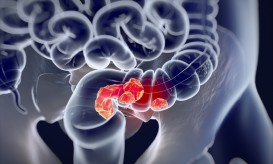

Αυτά είναι τα πρώιμα συμπτώματα που προκαλεί στους νέους ο καρκίνος του παχέος εντέρου

Τα ευρήματα νέας έρευνας, που βασίσθηκε σε περισσότερους από 5.000 ασθενείς, ηλικίας κάτω των 50 ετών.

Ο καρκίνος του παχέος εντέρου παρουσιάζει απρόσμενη αύξηση στην συχνότητα διάγνωσης και στους θανάτους μεταξύ των νεαρών λευκών Αμερικανών,...